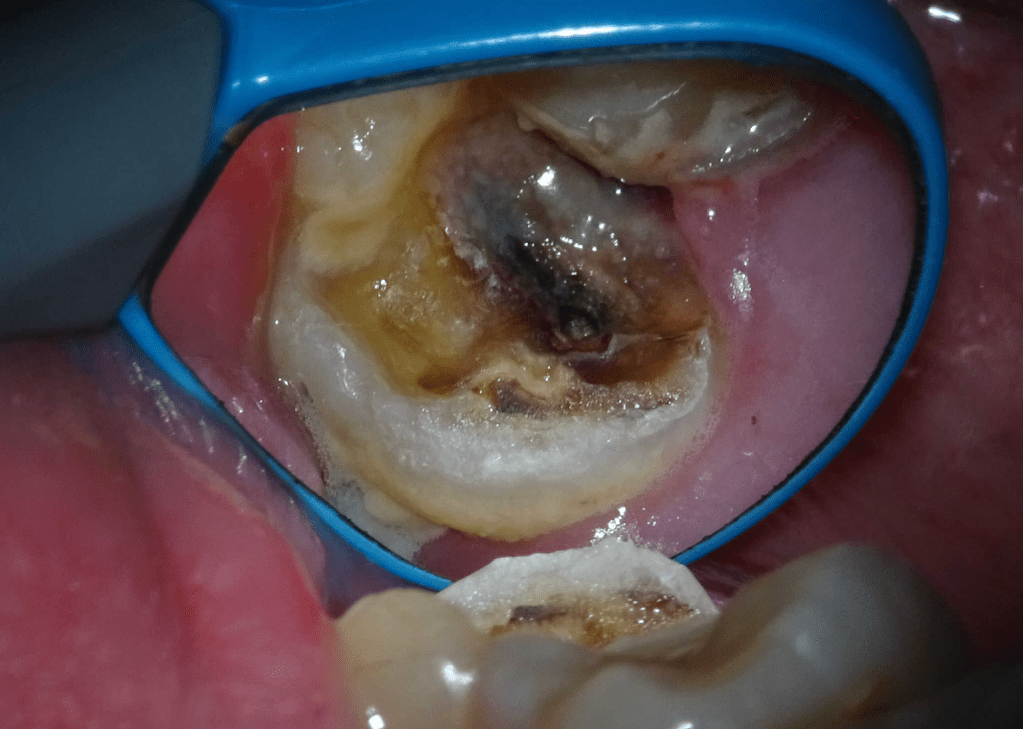

Diagnóstico de fisuras y fracturas

Fisura, remoción amalgama para explorar

Vertical root fracture